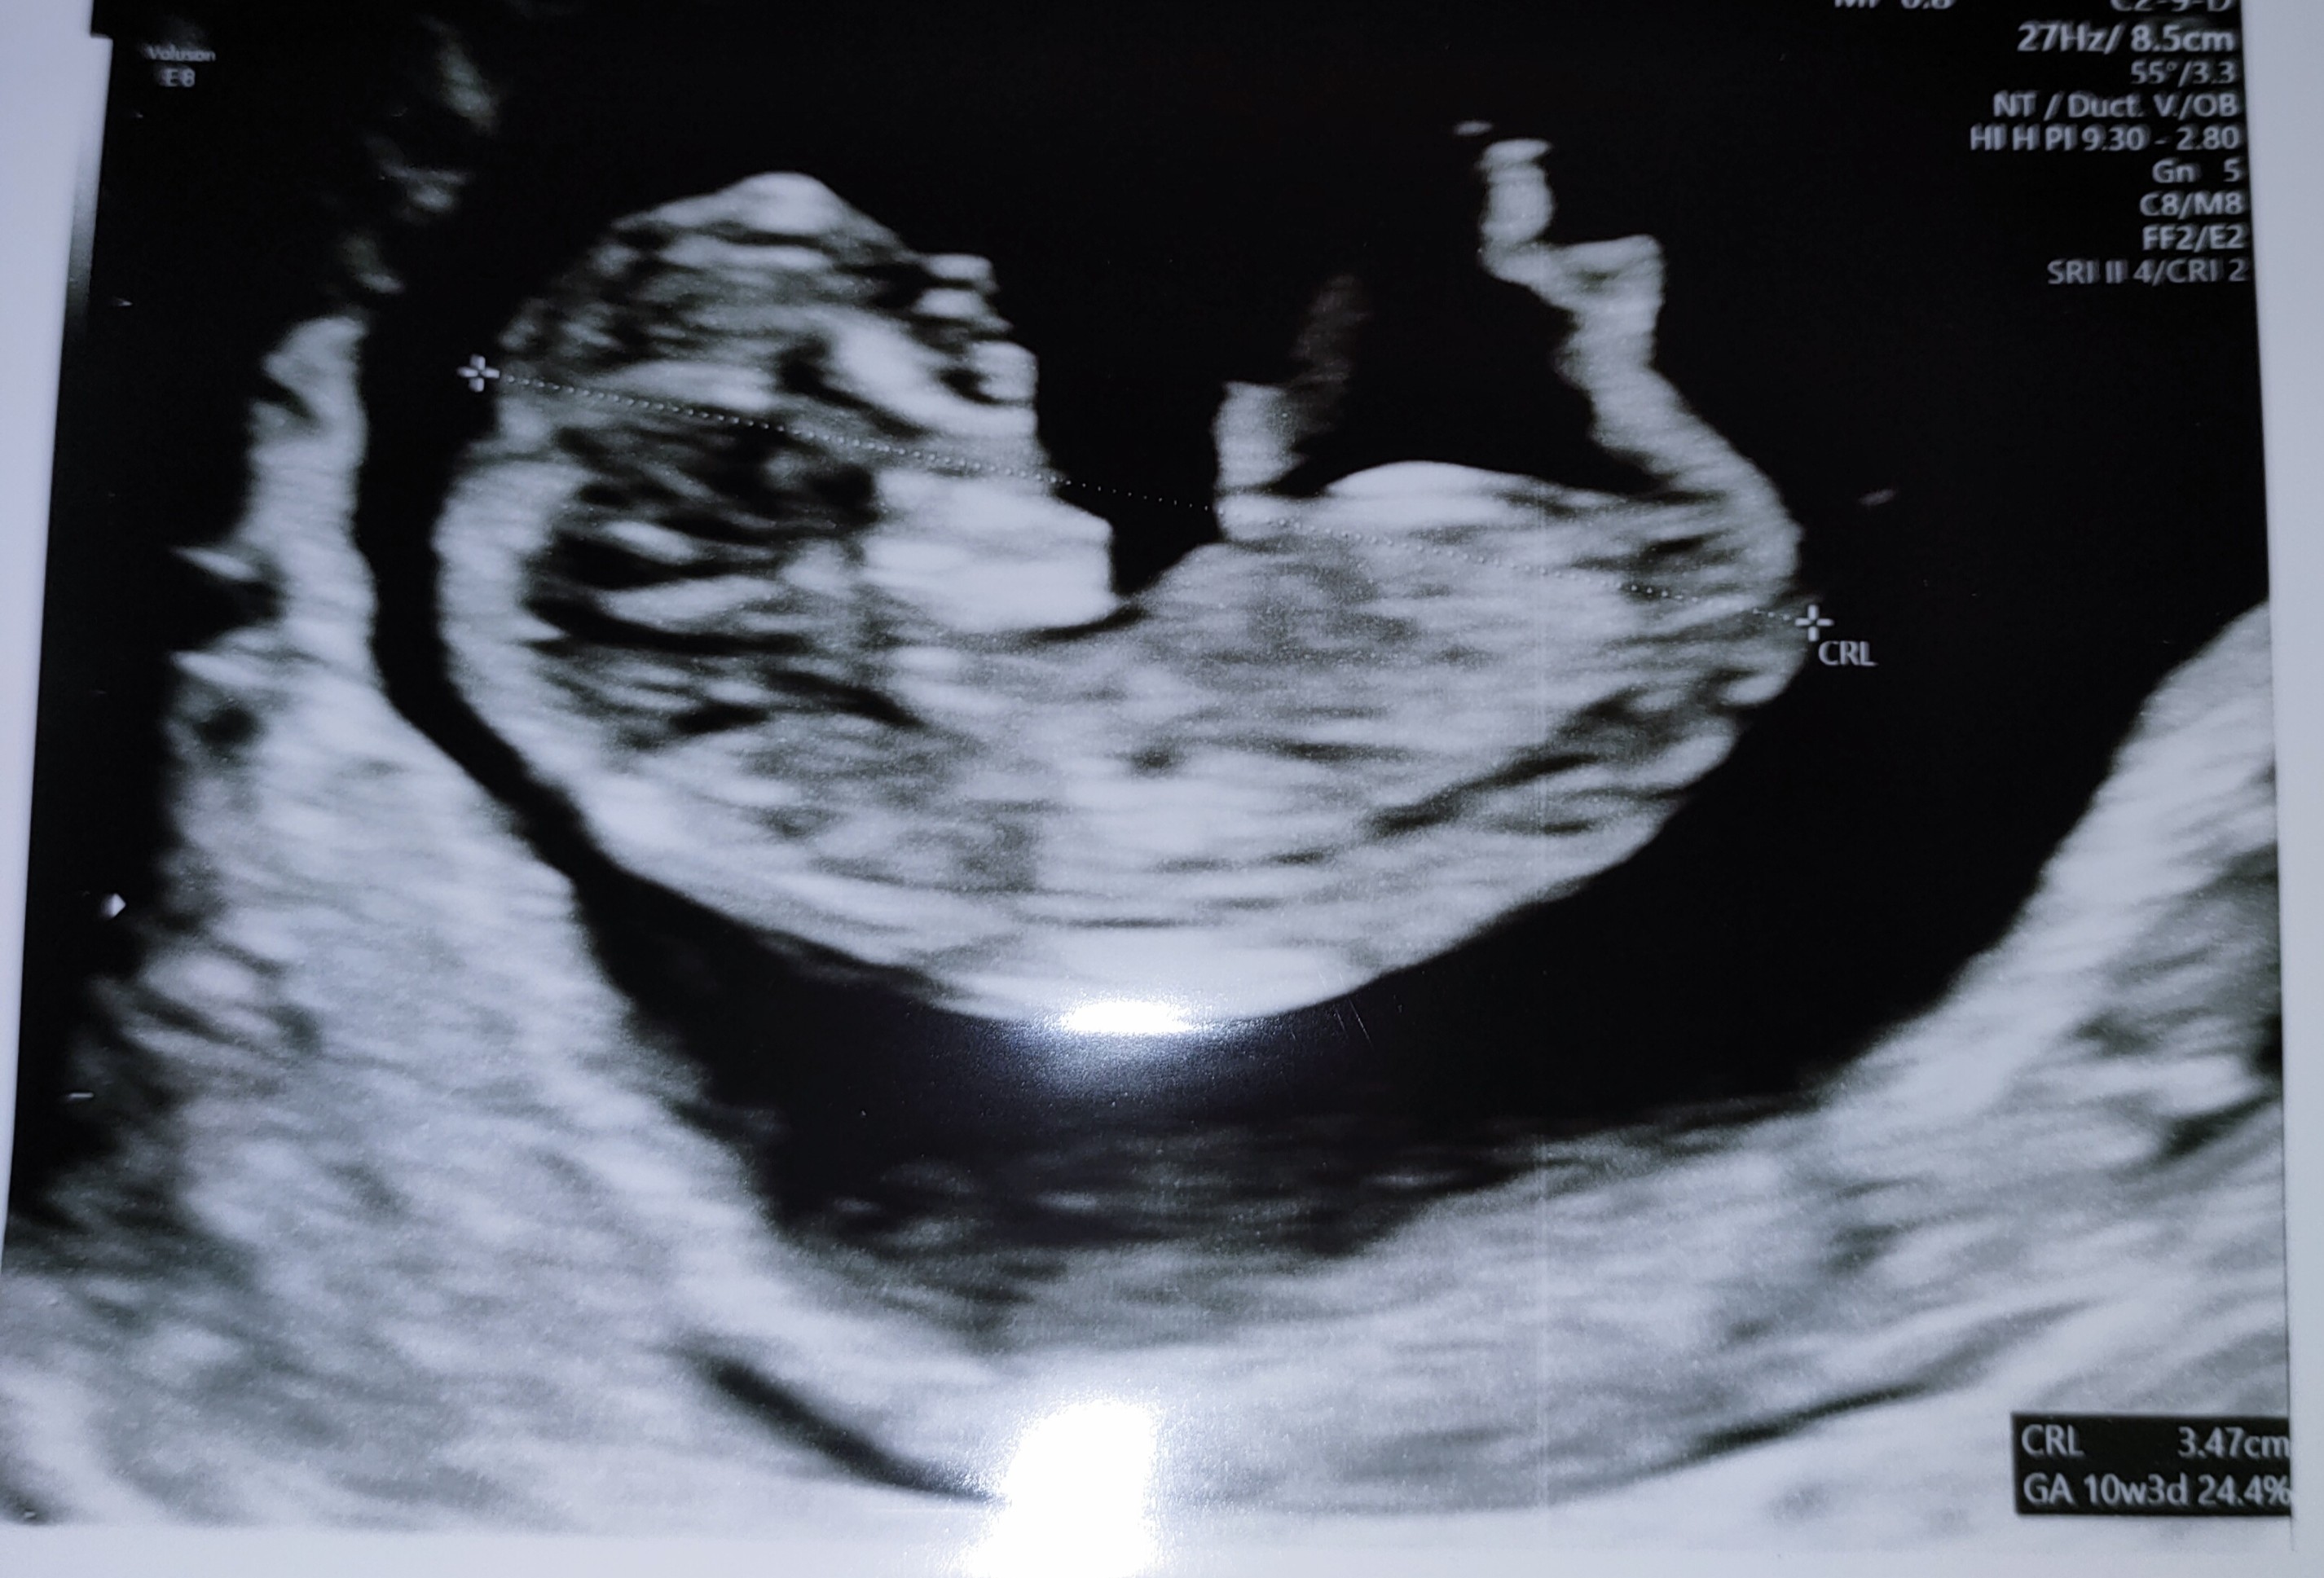

Daj znać jak poszło i który masz tydzieńJa właśnie przywiozłam od siostry jej stary ,co prawda trochę po przejściach ale będę testować